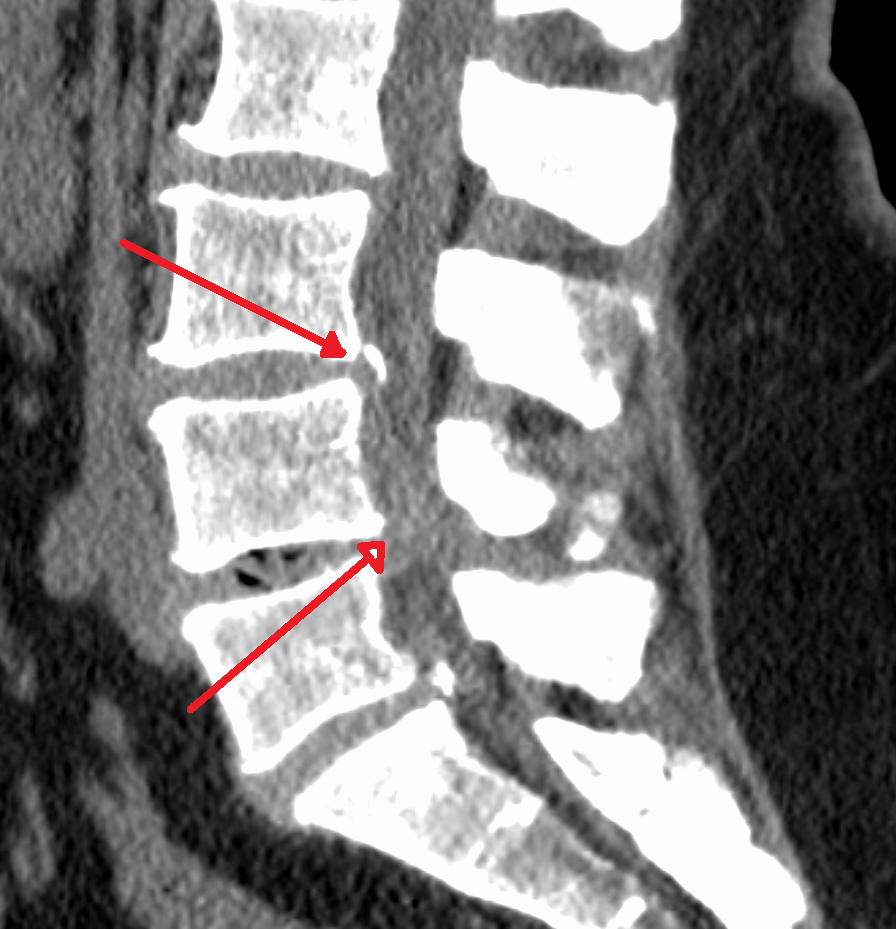

척추관은 척추 중앙의 관 모양(타원형, 삼각형) 속이 빈곳, 척추의 전방뼈와 후방뼈 사이에 있는 관뇌로부터 팔다리까지 신경(척수)이 지나가는 통로이다. 척추관협착증은 척추관(또는 신경근관, 추간공)이 좁아져서 척추 내 신경 구조물(척추신경근)에 압력을 가해 허리 통증(요통), 다리 통증 및 신경증세 일으키는 신경질환이다. 운동량이 많은 요추(요추부 협착증)와 경추(경추관 협착증)에서 발생한다.

척추변형 - 추간판의(수핵, 섬유륜) 퇴행성 변화(보통 30세이후부터)로 척추에 부착된 추간판이 떨어지며 골극을 형성한다.

척추관을 구성하는 후관절 돌기, 추궁, 황색인대의 변성으로 척추관의 전후좌우사방이 좁아진다.